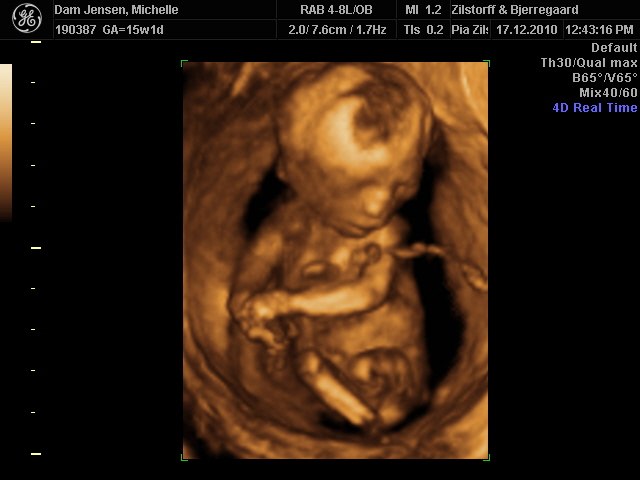

Det var så fantastisk at se hende i 3D selvom jeg ikke var længere henne end 15+1

men vægt mæssigt er hun 15+3 hehe så hun spiser godt må man sige

Alt var perfekt, hjerter, nyre, kranie tarme osv.. så vi var super stolte og glade